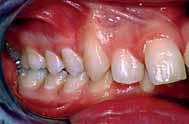

The oral hygiene was fair but needed improvement prior to orthodontic treatment. All teeth from the left permanent second molar to the right have erupted in both the upper and lower arches. The patient had carious lesions in both upper first molars, upper left second molar and lower left first molar. The maxillary arch was spaced with a midline diastema. Furthermore, there was mild lower labial segment crowding (4mm). The incisor relationship was Class II division 1, the overjet was 12 mm whereas the overbite was increased and complete to the palate

and causing trauma to the palatal mucosa. The centrelines were coincident and the buccal segment relationship was 1/2 unit Class II on both sides (Figure 2).